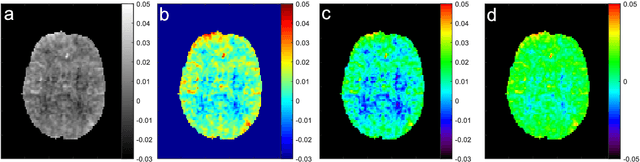

Abstract:Brain metastases occur frequently in patients with metastatic cancer. Early and accurate detection of brain metastases is very essential for treatment planning and prognosis in radiation therapy. To improve brain metastasis detection performance with deep learning, a custom detection loss called volume-level sensitivity-specificity (VSS) is proposed, which rates individual metastasis detection sensitivity and specificity in (sub-)volume levels. As sensitivity and precision are always a trade-off in a metastasis level, either a high sensitivity or a high precision can be achieved by adjusting the weights in the VSS loss without decline in dice score coefficient for segmented metastases. To reduce metastasis-like structures being detected as false positive metastases, a temporal prior volume is proposed as an additional input of the neural network. Our proposed VSS loss improves the sensitivity of brain metastasis detection, increasing the sensitivity from 86.7% to 95.5%. Alternatively, it improves the precision from 68.8% to 97.8%. With the additional temporal prior volume, about 45% of the false positive metastases are reduced in the high sensitivity model and the precision reaches 99.6% for the high specificity model. The mean dice coefficient for all metastases is about 0.81. With the ensemble of the high sensitivity and high specificity models, on average only 1.5 false positive metastases per patient needs further check, while the majority of true positive metastases are confirmed. The ensemble learning is able to distinguish high confidence true positive metastases from metastases candidates that require special expert review or further follow-up, being particularly well-fit to the requirements of expert support in real clinical practice.